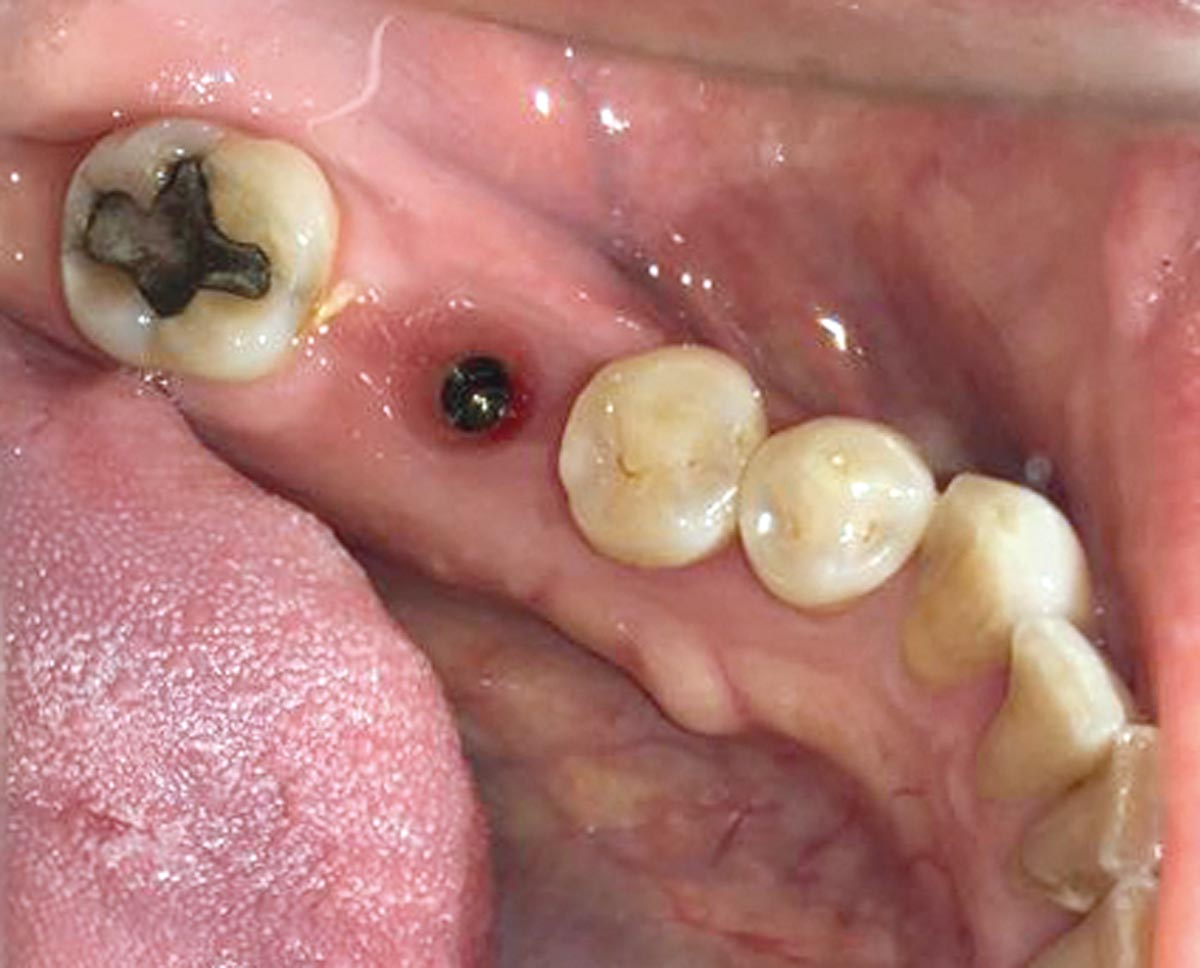

The patient presented with a terminal fracture of the crown tooth number 12